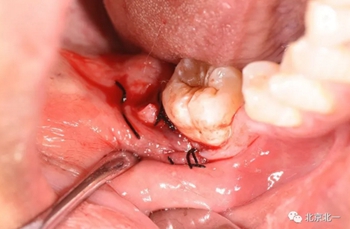

第二步:拔牙

切口設(shè)計(jì)關(guān)鍵點(diǎn)偏頰側(cè)。

去骨:原則暴露最大周徑線即可, 盡可能少去骨, 微創(chuàng)拔除。

截冠:有絲分裂至關(guān)重要。 保證微創(chuàng)下拔除智齒。

術(shù)后強(qiáng)調(diào)沖洗創(chuàng)口, 搔刮血液充盈。

縫合。